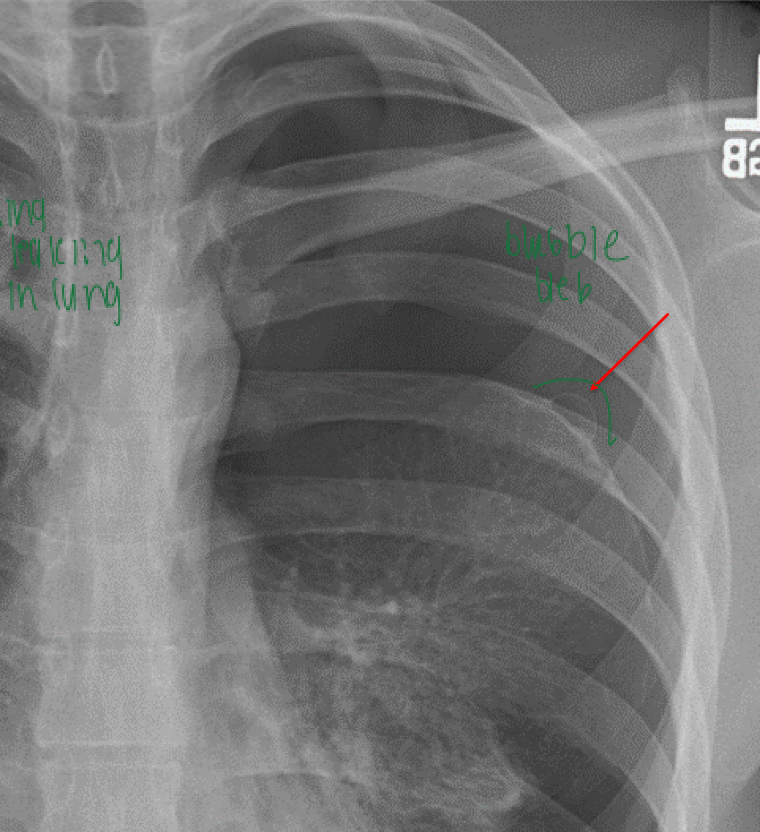

Rupture of apical sub-pleural bleb or

bullae

primary spontaneous PTX

risk factors for primary spontaneous pneumothorax